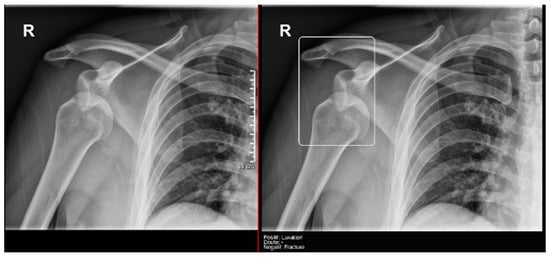

- Ankle and foot: On six occasions, Milvue marked the fracture variable as doubtful in cases with a bipartite medial sesamoid (two patients), an accessory sesamoid at the base of the 5th metatarsal, synphalangism, os peroneum, and os naviculare. (Figure 8).

- Hand: Milvue marked the fracture variable as doubtful in the case of multiple accessory ossicles.

- Wrist: On four occasions, Milvue marked the fracture variable as doubtful in cases of os paranaviculare, os trapezium secundarium, os ulnar styloid, and os paratrapezium. However, Milvue did not detect fractures in three cases of os ulnar styloid, two cases of accessory ulnar styloid, nor in cases of os hypolunatum and os epilunatum.